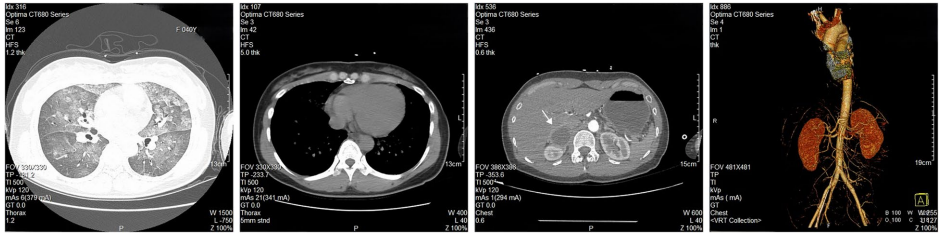

研究团队报道了一位40岁女性患者的惊险救治历程。患者突发严重胸痛伴休克,NT-proBNP(N末端脑钠肽前体)飙升至8588 pg/L,左心室射血分数(EF)骤降至40%。通过VA-ECMO与IABP构建"生命双保险"稳定循环后,CT发现右肾上腺4.7cm占位,24小时尿甲氧基肾上腺素(>2504μg/g Cr)等检测锁定嗜铬细胞瘤诊断。术后患者心功能完全恢复,验证了肿瘤切除对逆转心损伤的关键作用。

【影像学发现】

胸部CT显示双肺渗出性改变及右肾上腺低密度影